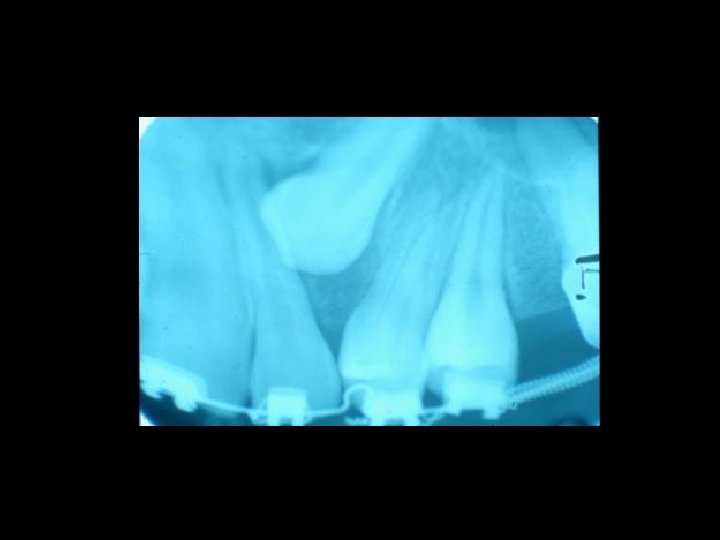

Il contenzioso PRINCIPALI AMBITI Ø Ø Ø La diagnosi La chirurgia orale La terapia conservativa Il trattamento delle anomalie dento-scheletriche La riabilitazione protesica

Responsabilità Ø Ø Ø Ø Garanzia di mezzi Garanzia di risultato Trattamento di soggetti in crescita Trattamento di soggetti al termine della crescita Comportamenti del paziente Risultato e recidiva Danni iatrogeni